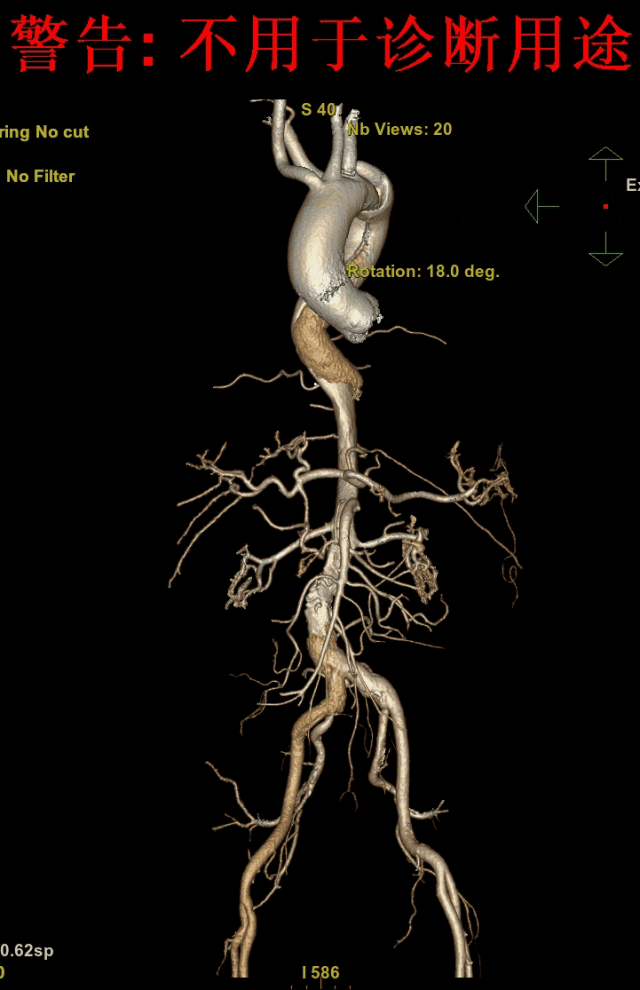

诊断:B型主动脉夹层、主动脉壁间血肿、迷走右锁骨下动脉。

手术方案:TEVAR+左锁骨下动脉重建+右锁骨下动脉重建,初步考虑用针刺原位开窗。

1.经左侧肱动脉和右侧肱动脉切开置管,然后右侧股动脉穿刺,覆膜支架沿左颈总动脉后缘释放,行TEVAR术。之后预备行右侧左锁骨下动脉原位开窗。

2.ARSA造影,尝试右侧针刺开窗。但由于该部位角度不好且路线较长,反复尝试操作后开窗非常困难。为避免发生血管夹层,果断放弃该操作。

3.左侧股动脉穿刺,导丝导管到达主动脉部位,利用Fustar引导,造影定位,在右锁骨下动脉开口膨大处进行顺序穿刺。同时利用右锁骨下动脉导管冒烟定位,顺利穿刺并成功。

右锁骨下动脉置入Viabahn支架和Smart Control支架,左锁骨下动脉同样进行针刺开窗,最终造影情况良好。